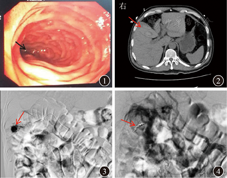

体温36.4 ℃,脉搏63次/min,呼吸频率为18次/min,血压123/78 mmHg。神志清楚、对答切题;皮肤无黄染、蜘蛛痣;左锁骨上等处浅表淋巴结未触及;巩膜轻度黄染,心肺无异常;腹部平坦,未见腹壁静脉曲张,腹部软,中上腹轻压痛,无反跳痛,肝脾未触及,肝区轻叩痛,腹水征阴性,肠鸣音正常;双下肢无浮肿。入院后查血常规示白细胞计数为7.05×109/L,中性粒细胞计数为5.70×109/L (占0.808),血红蛋白为114 g/L,血小板计数为13×109/L;血肌钙蛋白Ⅰ<0.010 ng/mL。血生物化学指标TBil为72.5 μmol/L,DBil为56.0 μmol/L,白蛋白为30.3 g/L,ALT为304 U/L,AST为183 U/L,GGT为591 U/L,ALP为245 U/L;血脂肪酶>2 000 U/L,血淀粉酶为377 U/L。入院后3 h患者突发呕吐暗红色血液1次,量约500 mL,呕吐后上腹部疼痛无缓解。体格检查示体温36.5 ℃,脉搏80次/min,呼吸频率为19次/min,血压90/60 mmHg,神志清楚,贫血面容,睑结膜苍白,巩膜轻度黄染,心肺未见明显异常,腹部平坦,中上腹轻压痛,无反跳痛,叩诊鼓音,肝区轻叩痛,肾区无叩击痛,移动性浊音为阴性,肠鸣音为4次/min。病床旁行急诊胃镜检查发现,胃腔内大量血性内容物和血凝块、食物残渣,清除血凝块,冲洗胃腔后逐个部位检查,发现十二指肠乳头部有血液渗出,考虑胆道出血(图1)。急诊全腹CT平扫+增强扫描显示胆囊内高密度影,出血可能;肝内外胆管稍扩张;胰头区少许渗出性改变(图2、图3)。急诊选择性数字减影血管造影(digital subtraction angiography,DSA)检查右肝动脉分支血管可见不规则囊状假性动脉瘤改变,造影剂明显滞留,并见造影剂外渗现象(图4)。

注:CT为计算机断层扫描;DSA为数字减影血管造影

介入科林征宇主任医师:DSA是胆道出血的首选手段,其不仅可用于诊断,还能直接栓塞出血部位,发挥治疗作用[7]。胆道出血的直接表现为动脉期造影剂呈团状或柱状外溢,肝实质内出现片状造影剂影,即动脉-胆道漏征象,间接表现则为假性动脉瘤[8]。经导管动脉栓塞术的优点在于止血迅速,效果持久、可靠,不成功者可再行栓塞治疗。使用金属微弹簧圈填充闭合假性动脉瘤处血管的近端和远端,可使胆道出血得到妥善治愈。但受胆道出血速度制约,当出血速度>30 mL/h时才可发现造影剂溢出,实施栓塞,因此必要时需联合CT、胃镜等检查手段。本例患者行DSA检查示右肝动脉分支血管可见一不规则囊状假性动脉瘤,造影剂明显滞留,并见造影剂外渗现象。根据DSA检查结果,胆道出血、肝假性动脉瘤诊断明确,治疗上予弹簧圈栓塞假性动脉瘤的载瘤供血动脉,并用明胶海绵颗粒加强栓塞,后DSA检查造影见假性动脉瘤消失。